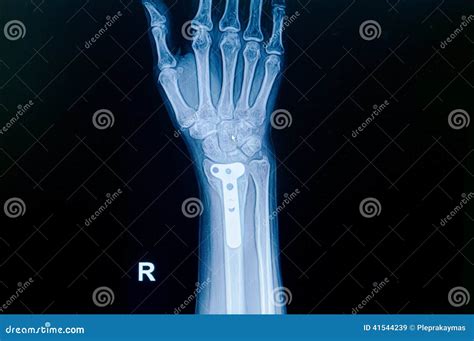

Injuries can happen unexpectedly, and one of the most common and painful injuries is an Xray Broken Hand. Whether it's from a fall, a sports accident, or a workplace mishap, a broken hand can significantly impact daily activities and quality of life. Understanding the causes, symptoms, diagnosis, and treatment options for an Xray Broken Hand is crucial for effective management and recovery.

A broken hand, often diagnosed through an X-ray, involves a fracture in one or more of the bones in the hand. The hand is composed of 27 bones, including the metacarpals, phalanges, and carpals. Each of these bones can be susceptible to fractures, which can range from minor cracks to severe breaks.

• X-rays: X-rays are the primary imaging tool used to confirm the presence and type of fracture. They provide detailed images of the bones and can help determine the severity of the injury.

• Surgery: In severe cases, surgery may be required to realign the bones and stabilize the fracture with plates, screws, or pins.